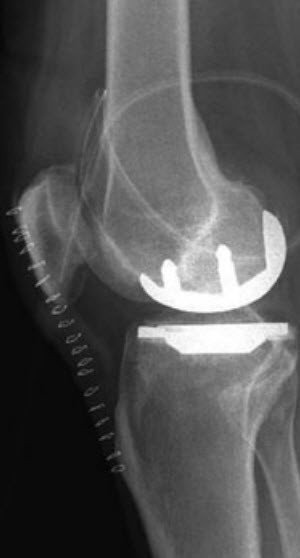

If only the kneecap or the inner or outer part of the knee joint is affected by wear, partial joint replacement (sled prosthesis/unicompartmental knee arthroplasty) may be performed. Important prerequisites for this indication are that the osteoarthritis is primarily limited to a single section of the knee joint and that the knee ligaments are still functional.

Compared to a total prosthesis, a partial prosthesis generally results in better mobility and a more natural-feeling knee. The procedure is also less invasive as all the ligament structures and the joint parts that are still healthy are preserved, which facilitates rapid recovery after surgery.

The knee joint must be exposed from the front by making an incision in the skin of approx. 15 cm long. The worn surfaces of the joint are worked on according to a special cutting plan and prepared for the artificial surface replacement. The exact size and type of prosthesis are selected based on preoperative X-rays and measurements taken during surgery. The artificial joint is then usually anchored in the bone with bone cement.